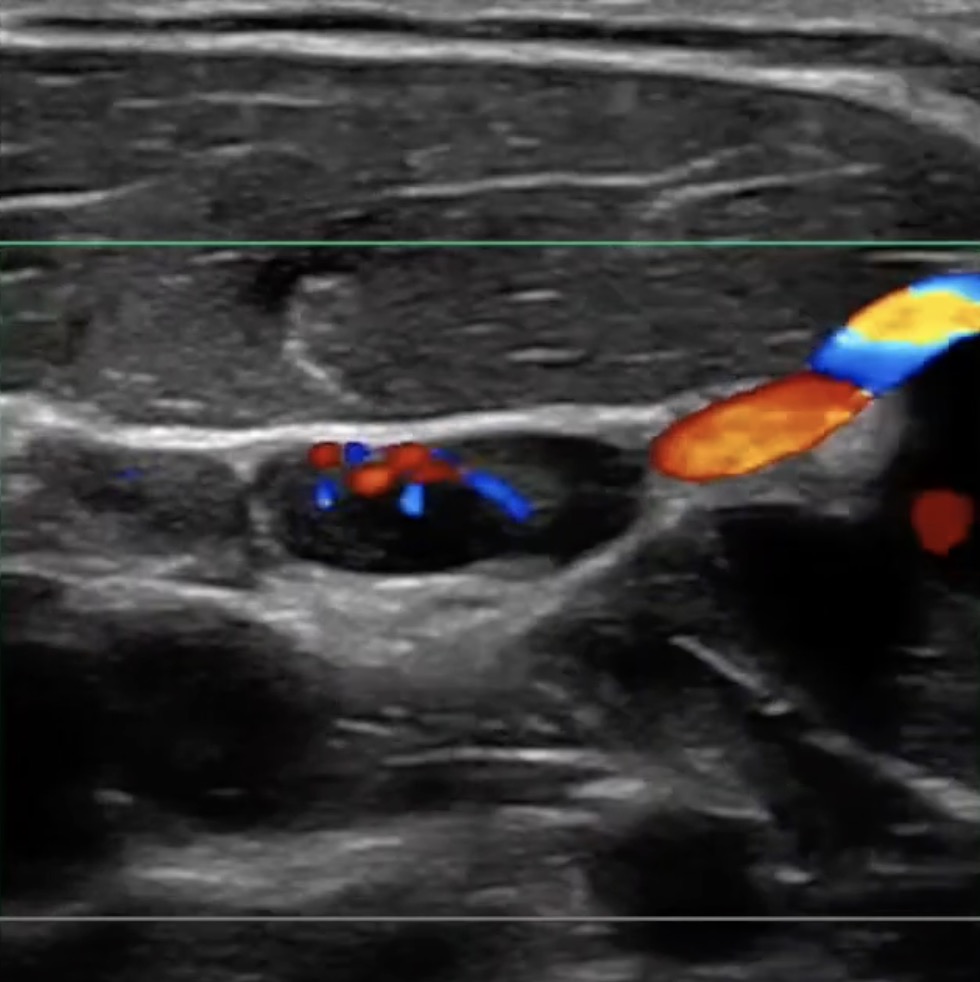

Another unique and patented engineering breakthrough that differentiates ZST from traditional hardware-based beamforming platforms is automated digital Sound Speed Compensation (SSC). Historically, ultrasound imaging systems have been calibrated to the inaccurate assumption that ultrasound propagates through all human soft tissue at a velocity of 1,540 meters per second. In fact, many factors affect the actual speed of sound in a particular tissue and failure to compensate for these differences diminishes and limits spatial and contrast resolution in conventional ultrasound systems. At the touch of a button, SSC automatically samples the tissue being examined and recalibrates the software to reflect its specific speed of sound. The resulting enhancements in image quality provide another powerful clinical tool that increases diagnostic confidence, especially when examining diseased organs and structures at deeper depths.

Compare and the difference is clear. Enhanced spatial resolution in a tissue-equivalent pin phantom without Sound Speed Compensation (A) and with Sound Speed Compensation (B).